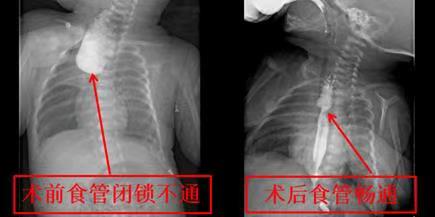

在吴缤副主任医师、麻醉科以及手术室的多方协同努力下,田宝宝于1月18日晚上接受了手术治疗,手术结束已是将近凌晨3点。经过3个小时的不懈努力,吴缤副主任医师顺利为田宝宝打通了生命通道。对于田宝宝而言,这是改变命运的3个小时,而对于吴缤副主任医师来说,这亦是突破性的3个小时,医院的食管闭锁手术就此进入了“胸腔镜微创时代”。田宝宝在NICU医护人员的精心呵护下,肺炎逐渐好转,顺利度过了术后危险期,并于术后第9天转回32病区进一步治疗,看着田宝宝复查的上消化道造影检查结果,吴缤副主任医师难以掩饰心中的喜悦。从术后10天开始少量饮水,目前已经可以吃到正常奶量,很快将要出院。看着大口吃奶的田宝宝,让原本坐立不安的父母露出了久违的笑容。为了表示感谢,家长为吴缤副主任医师及三十二病区全体医护送上了锦旗。